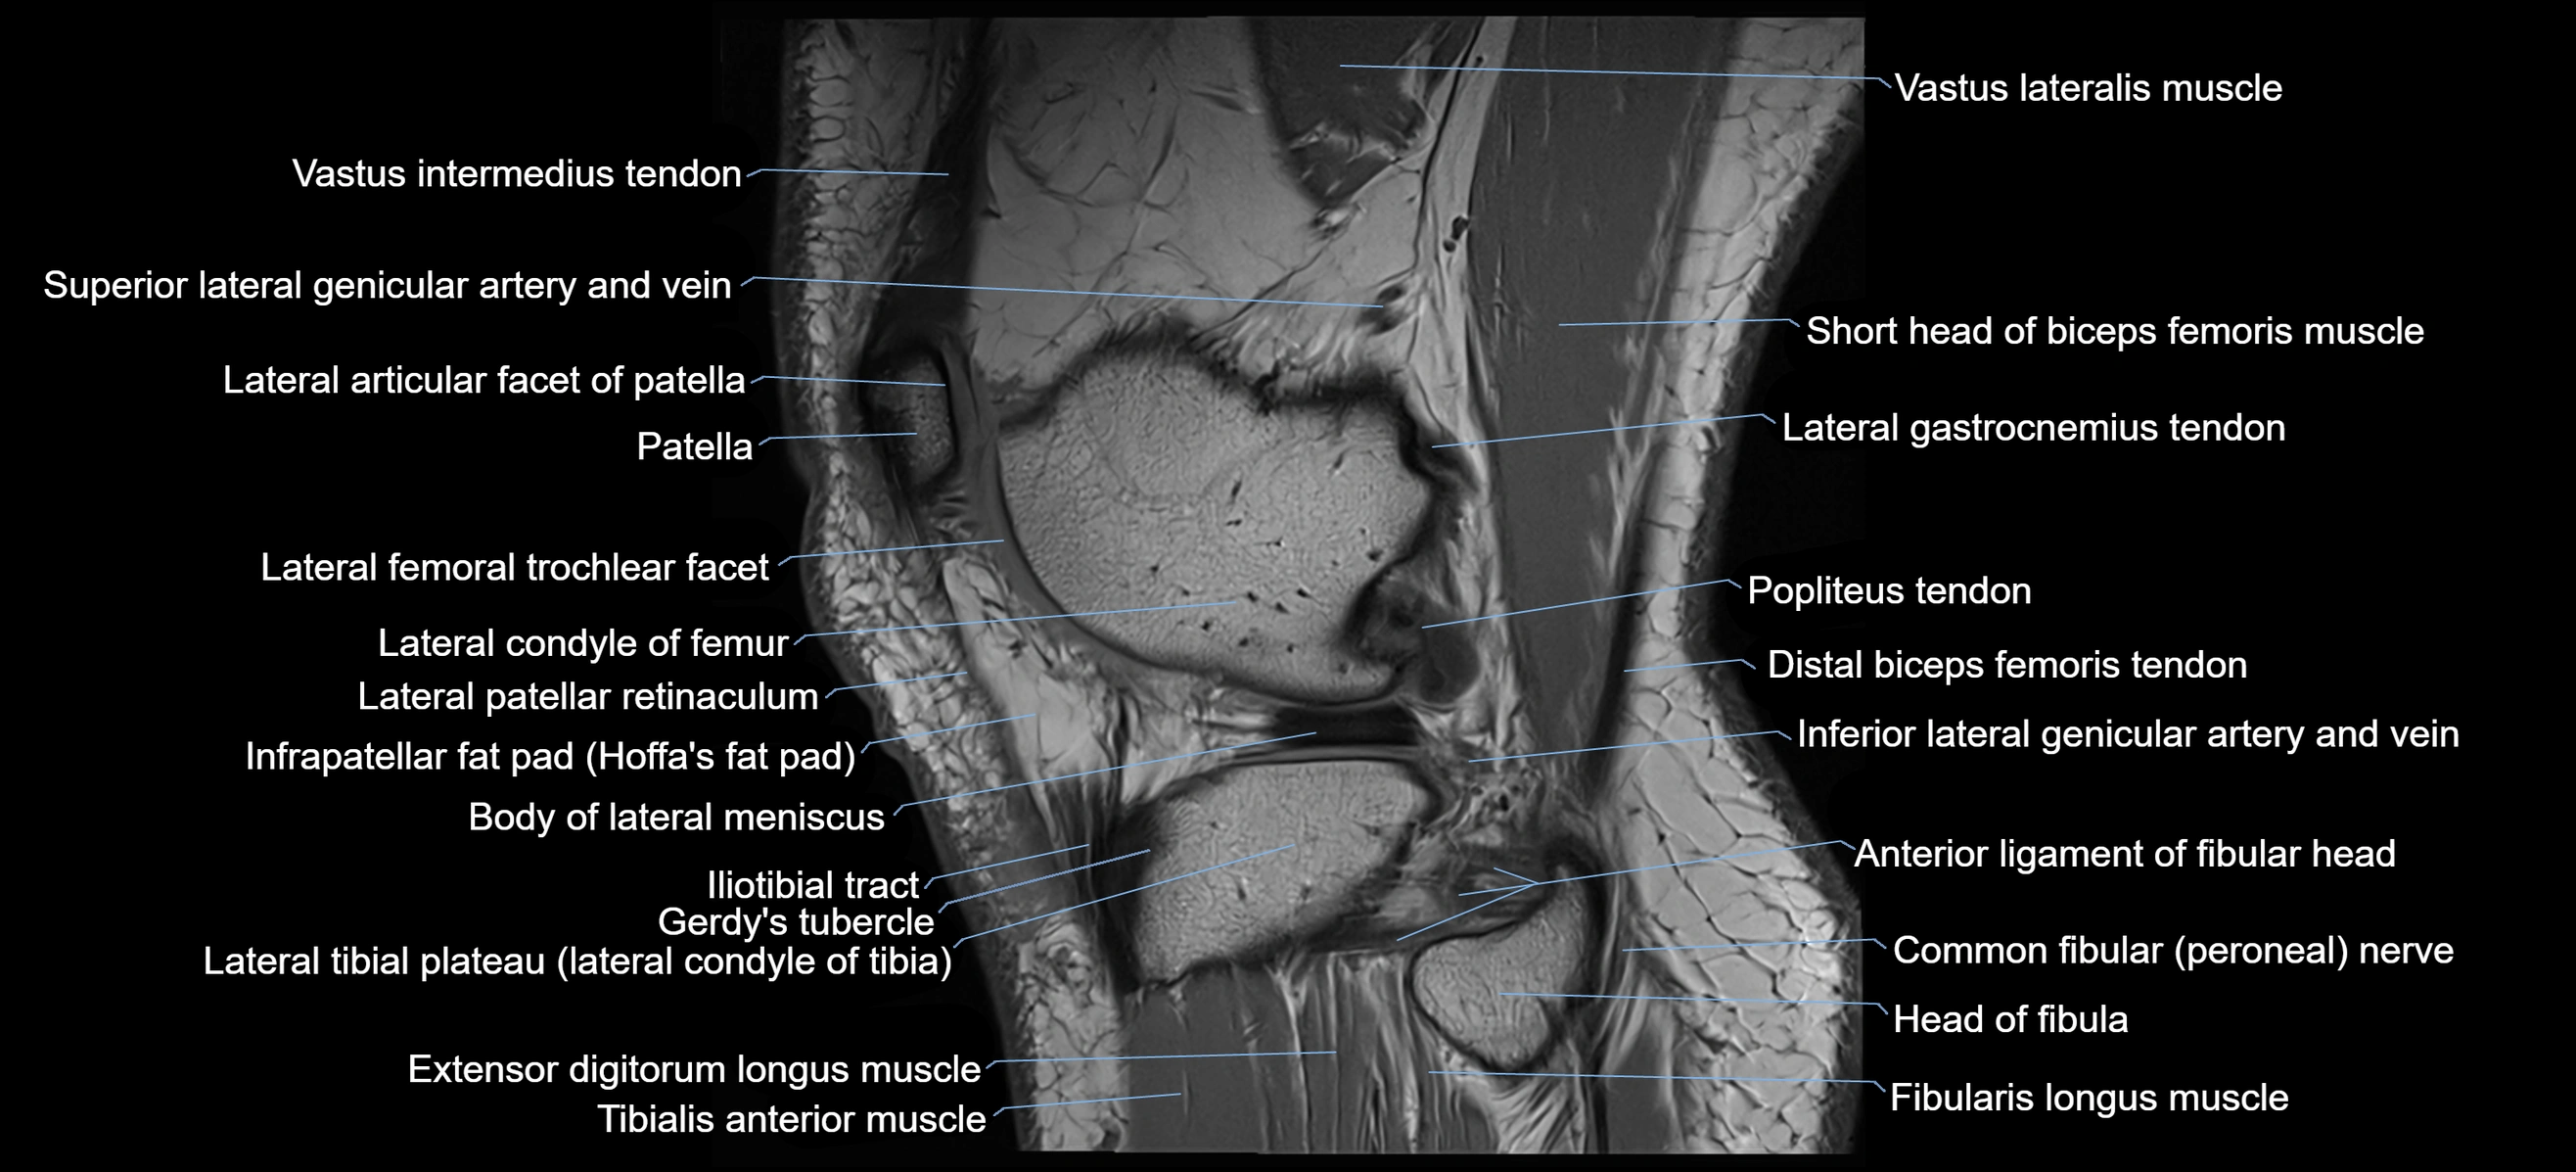

- Body of lateral meniscus

- Distal biceps femoris tendon

- Distal vastus lateralis tendon

- Gerdy’s tubercle

- Head of fibula

- Inferior lateral genicular artery

- Inferior lateral genicular vein

- Lateral articular facet of patella

- Lateral condyle of femur

- Lateral gastrocnemius tendon

- Lateral patellar retinaculum

- Lateral sural cutaneous nerve

- Lateral tibial plateau